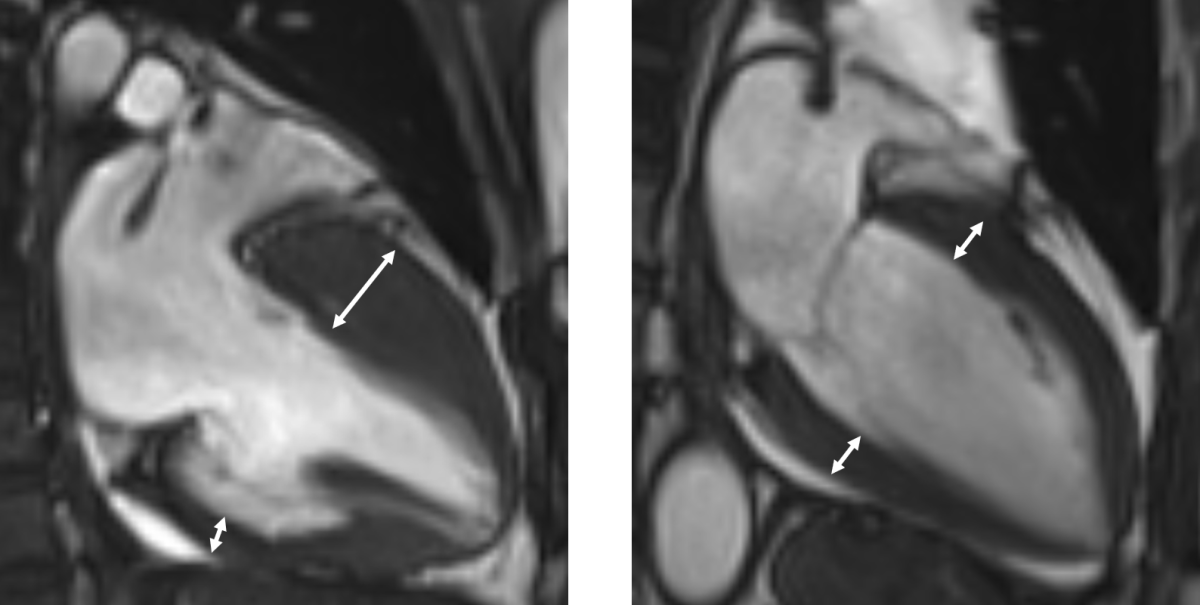

ºñÈļº ½É±Ùº´ÁõÀº ½ÉÀå±ÙÀ°(½É±Ù)ÀÌ ºñÁ¤»óÀûÀ¸·Î µÎ²¨¿öÁö´Â ÁúȯÀÌ´Ù. ½É±ÙÀÌ µÎ²¨¿öÁö¸é ±ÙÀ°ÀÇ ¼öÃà°ú ÀÌ¿ÏÀÌ ¿øÈ°ÇÏÁö ¾Ê¾Æ ºÎÁ¤¸ÆÀÌ ¹ß»ýÇϰí, ¶§·Î´Â Ä¡¸íÀû ºÎÁ¤¸ÆÀÌ ¹ß»ýÇØ µ¹¿¬»ç·Î À̾îÁú ¼ö ÀÖ¾î °¢º°ÇÑ ÁÖÀǰ¡ ÇÊ¿äÇÏ´Ù.

Áø´ÜÀº ½ÉÀåÃÊÀ½ÆÄ, ÀÚ±â°ø¸í¿µ»ó µî ¿µ»ó°Ë»ç¸¦ ÅëÇØ ÀÌ·ïÁø´Ù. ºñÈÄµÈ ½É±Ù ³»¿¡ ¼¶À¯È°¡ ÁøÇàµÅ Àְųª, ±ÙÀ°Á¶Á÷ÀÌ Áö¹æÁ¶Á÷À¸·Î º¯¼ºÀÌ µÅ ÀÖ´Â »óŰ¡ °üÂûµÈ´Ù. ÇÏÁö¸¸ ÀÌ °°Àº Á¶Á÷º¯¼ºÀÌ ¾ø´Â ºñÈļº ½É±Ùº´Áõµµ ÀÖ´Â ¸¸Å Àü¹®ÀÇÀÇ Á¾ÇÕÀû ÆÇ´ÜÀÌ Áß¿äÇÏ´Ù.